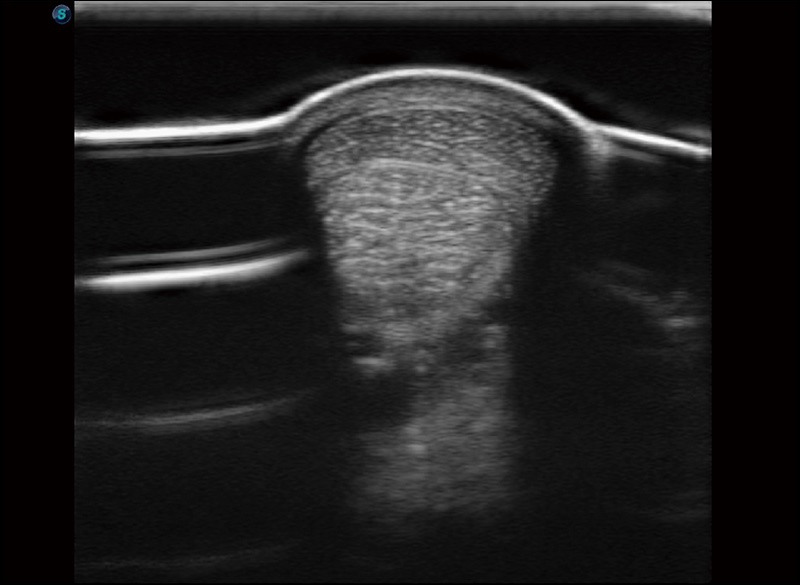

α1卓越的图像质量和便捷的工作流程,使每位宠物医生都能轻松扫查。其全面的兽用应用功能和紧凑型的结构设计,可以满足动物检查的多种需要。专业的预设检查模式和多领域测量软件包有助于为不同类型的动物提供检查, 让宠物医生能够出色的完成工作。

人机工程学设计

15.6英寸高清显示器

灵活可调节的显示器

防水面板设计

快速启动

静音系统